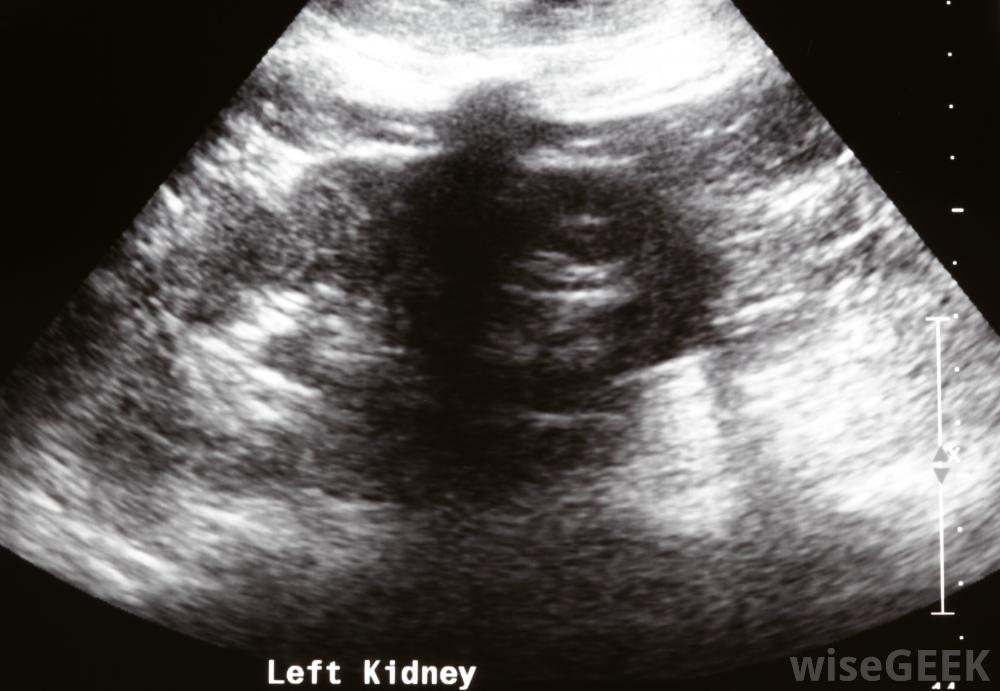

急性肾功能衰竭的确切原因可以通过对该器官的诊断成像来确定肾功能衰竭通常会引起立即症状,可能是轻微到严重的。大多数急性肾衰竭的早期患者会注意到他们不能排尿、感到虚弱或昏昏欲睡,呼吸困难。严重的情况,如癫痫发作或昏迷,可能很快出现或在其他症状确定后发展。通常需要紧急治疗,以防止肾功能完全丧失和其他慢性健康问题。在某些情况下,如果不及时就医,急性肾功能衰竭可能致命立即寻求。

可进行肾脏超声检查,以确认急性肾功能衰竭的诊断医生和护士通常通过进行体格检查和检查血液和尿液样本中是否有异常浓度的矿物质来检查急性肾功能衰竭。专家也可以进行超声波或计算机断层扫描来确认诊断并试图确定肾衰竭的确切原因。了解肾脏问题的根本原因对于决定最合适的治疗方法至关重要。